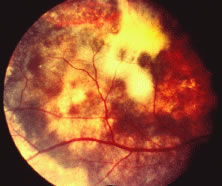

Both herpes simplex virus type 1 and herpes simplex virus type 2 (HSV-1, HSV-2) may cause ARN.20–22 In a single report, CMV particles were identified in and cultured from the retina of an enucleated eye of a nonimmunosuppressed patient suffering from bilateral ARN.23 VZV has been reported most frequently as the viral etiologic agent of ARN.2,3,24–27 We have demonstrated herpesvirus family viral particles in endoretinal biopsy specimens taken from patients in the active stage of the disease who showed an enormous viral load (Fig. 4). These studies, combined with the failure of many enucleated eyes with ARN to demonstrate evidence of viral particles, indicate that the virus is present only in the active stages of the disease and that a gliotic retina will not demonstrate the etiologic agent.28